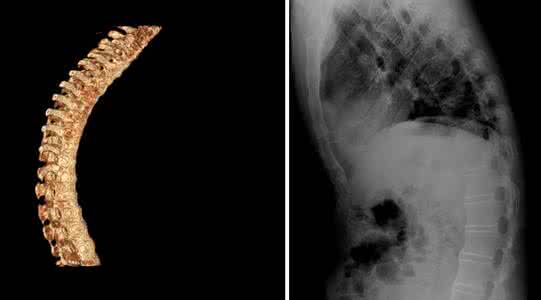

强直性脊柱炎容易在冬季的时候发病,患者自身也会感觉到病情,在冬季的时候病情往往就会加重。这与天气寒冷潮湿有关,与患者平时不好的生活习惯和对疾病的认识的缺乏也是很有关的。该病容易带来关节畸形的情况,患者在冬季的时候更要注意关节的锻炼。